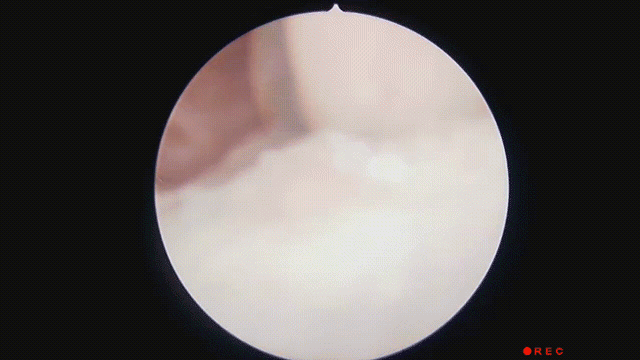

为啥小小的鱼刺,到了国外就找不着也拔不出了呢?中国医生咋就那么会拔鱼刺呢?中国医生厉害的拔鱼刺技术,根本原因是中国人吃了太多「鱼刺」。说起吃鱼,中国人想到的更多是剁椒鱼头、糖醋鲤鱼,还有妈妈熬的那碗鲫鱼豆腐汤。它们有一个特点:都是淡水鱼,刺多。而欧美国家更多食用的是海洋鱼类。海水鱼与淡水鱼的主要区别之一就是缺少肌间骨,也是吃鱼会不会卡鱼刺的关键。这是 X 光下的一条淡水鱼。肌间骨是那些 I 字形、Y 字形的小刺,是一次次把我们送去急诊室的罪魁祸首。欧美地区很少吃淡水鱼,留给欧美医生实践处理小鱼刺卡喉的机会实在是太少,操作经验不足且不灵活。以美国为例,全部消化道气道异物发生率不高,小孩子的异物多数是硬币,成年人多数是肉块或者鸡骨,鱼刺占比低到基本不统计。这就决定了他们的卡鱼刺处理策略,还是沿袭大块异物诊治流程,提倡首先通过 X 光、CT 等影像学检查确定位置。然而影像学观察小鱼刺难度很大,大量的时间浪费在「找刺」上。就算找到了,拔鱼刺也不怎么熟练。因此在美国拔一根鱼刺真就有可能折腾十几个小时。5 年来,仅仅是发表的特殊案例数量就有 24529 例,真实发生的鱼刺卡喉数都数不过来。很多医院一晚上急诊都能处理两位数的鱼刺卡喉,节假日还会翻倍。面对这样的现实,中国医生在处理鱼刺方面必须要更快、更精准。中国医生通常会绕开 X 光等检查的步骤,借助于更为熟练掌握的各种喉镜技术直击痛点,并且在取异物器材方面推陈出新,一切都为了更快的搞定鱼刺,减少痛苦。一批批一代代医生的努力和实践,让一根鱼刺在中国的急诊不再是多学科疑难杂症,而是值班医生的驾轻就熟。普通的鱼刺,坐下→张嘴→好了,最快几分钟就解决了。海量的患者需求,最终造就了中国医生精湛的鱼刺处理技艺。中国拔鱼刺主力是急诊耳鼻喉医生,口腔和消化科医生则负责处理少数不走寻常路的鱼刺。如果你卡了鱼刺去往急诊,接待你的大概率会是耳鼻喉科医生。一般情况下,医生不会让你去做 X 光等其他检查,只需要坐好在诊室里,张开嘴巴。少数鱼刺会卡在扁桃体表浅处或舌背上,张嘴就能看到。没有看到的话,就要压住舌背,借助于间接喉镜观察。那个亮亮的小镜子就像潜艇的潜望镜,可以扩大视野,看清楚直视看不到的地方。如果还是没有看到,刺入更深,会使用真正的电子喉镜,从鼻腔进入咽喉仔细探寻。容易看到的那些鱼刺,拔出也相对容易,一根镊子就能又稳又准地解决问题。更深部分的鱼刺,就要借助于更犀利的工具从内镜过去拔鱼刺。为了拔得更顺手,中国医生还推动了异物抓取钳的改进,从简单的单一样式发展到今天的五花八门。这些形形色色的异物抓取钳,适合用来处理不同直径、不同位置的鱼刺。粗的、细的,深的、浅的,上面的、下面的……没有鱼刺能轻松逃过中国医生手里的抓取钳。如果鱼刺不幸刺入食管或者更深处的胃,处置原则也是一样的,只是操作用内镜从喉镜换成胃镜而已。总之不管用什么手段,鱼刺都逃不出中国医生的手掌心。注:费用参考来源于多地不使用电子喉镜时的基础收费,请以实际情况为准。特殊情况下,医生也有可能为了安全先安排 X 光等检查。虽然中国医生很会拔鱼刺,但仍有很多鱼刺成为了我们的健康大患。有些鱼刺扎得实在太深,穿透咽喉或者食管壁,刺破身体内部,那就糟糕了。拔鱼刺专家们给到大家一些原则:有选择的话,尽量少吃有小刺的鱼;吃鱼时专心致志剔鱼刺,别看剧别说话;能单独吃鱼,就别混在米饭里一口吞;卡住了尽快去医院,别用醋和馒头的土方法自救。还要谢谢生物学家们,他们正在利用基因技术研发没有肌间骨的淡水鱼。未来如果大规模上市,大口吃鱼就更有底气,各家医院的夜间鱼刺门诊可能就要撤销了。不过中国医生这门手艺可能还不会放下,因为除了尖锐的鱼刺卡喉,还有另外一种刺入食管的尖锐异物——枣核,也是急诊常客。希望生物学家们什么时候也惦记一下。致谢:本文经中国科学技术大学附属第一医院耳鼻咽喉科主治医师 潘春晨 专业审核[1]中国科学报:10 年做出原始创新成果!无小刺鱼诞生全揭秘[2]中华医学会消化内镜学分会. 中国上消化道异物内镜处理专家共识意见(2015年,上海). [3]Kim HU. Oroesophageal Fish Bone Foreign Body. Clin Endosc. 2016 Jul;49(4):318-26. doi: 10.5946/ce.2016.087. Epub 2016 Jul 26. PMID: 27461891; PMCID: PMC4977739.[4]https://www.entclinic.sg/blog/fish-bones-in-the-throat/[5]Wei X, Wang J, Xu W. Emergency management of jujube pit esophageal impactions using rigid esophagoscopy in the aged[J]. Laryngoscope Investigative Otolaryngology, 2021, 6(6): 1332-1338.[6]马良骁, 董在杰, 苏胜彦, 等. 鱼类肌间刺的研究进展[J]. 江苏农业科学, 2012, 40(4): 234-235.丁香园是面向医疗从业者的专业平台,以「助力中国医生」为己任。下载「丁香园 App」可以和同行讨论病例 ,在线学习公开课,使用用药助手等临床决策工具,在丁香人才找可靠医疗岗位。